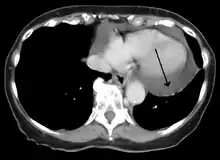

Cardiac CT and MRI scans: cross-sectional imaging with computed tomography (CT) can help localize and quantify the effusion, especially in a loculated effusion (a effusion contained to one area).[10] CT imaging also helps assess for pericardial pathology (pericardial thickening, constrictive pericarditis, malignancy-associated pericarditis).[1] Whereas cardiac MRI is reserved for patients with poor echocardiogram findings and for assessing pericardial inflammation, especially for patients with continued inflammation despite treatment.[4] CT and MRI imaging can also be used for continued follow up on patients.

A CT scan showing a pericardial effusion